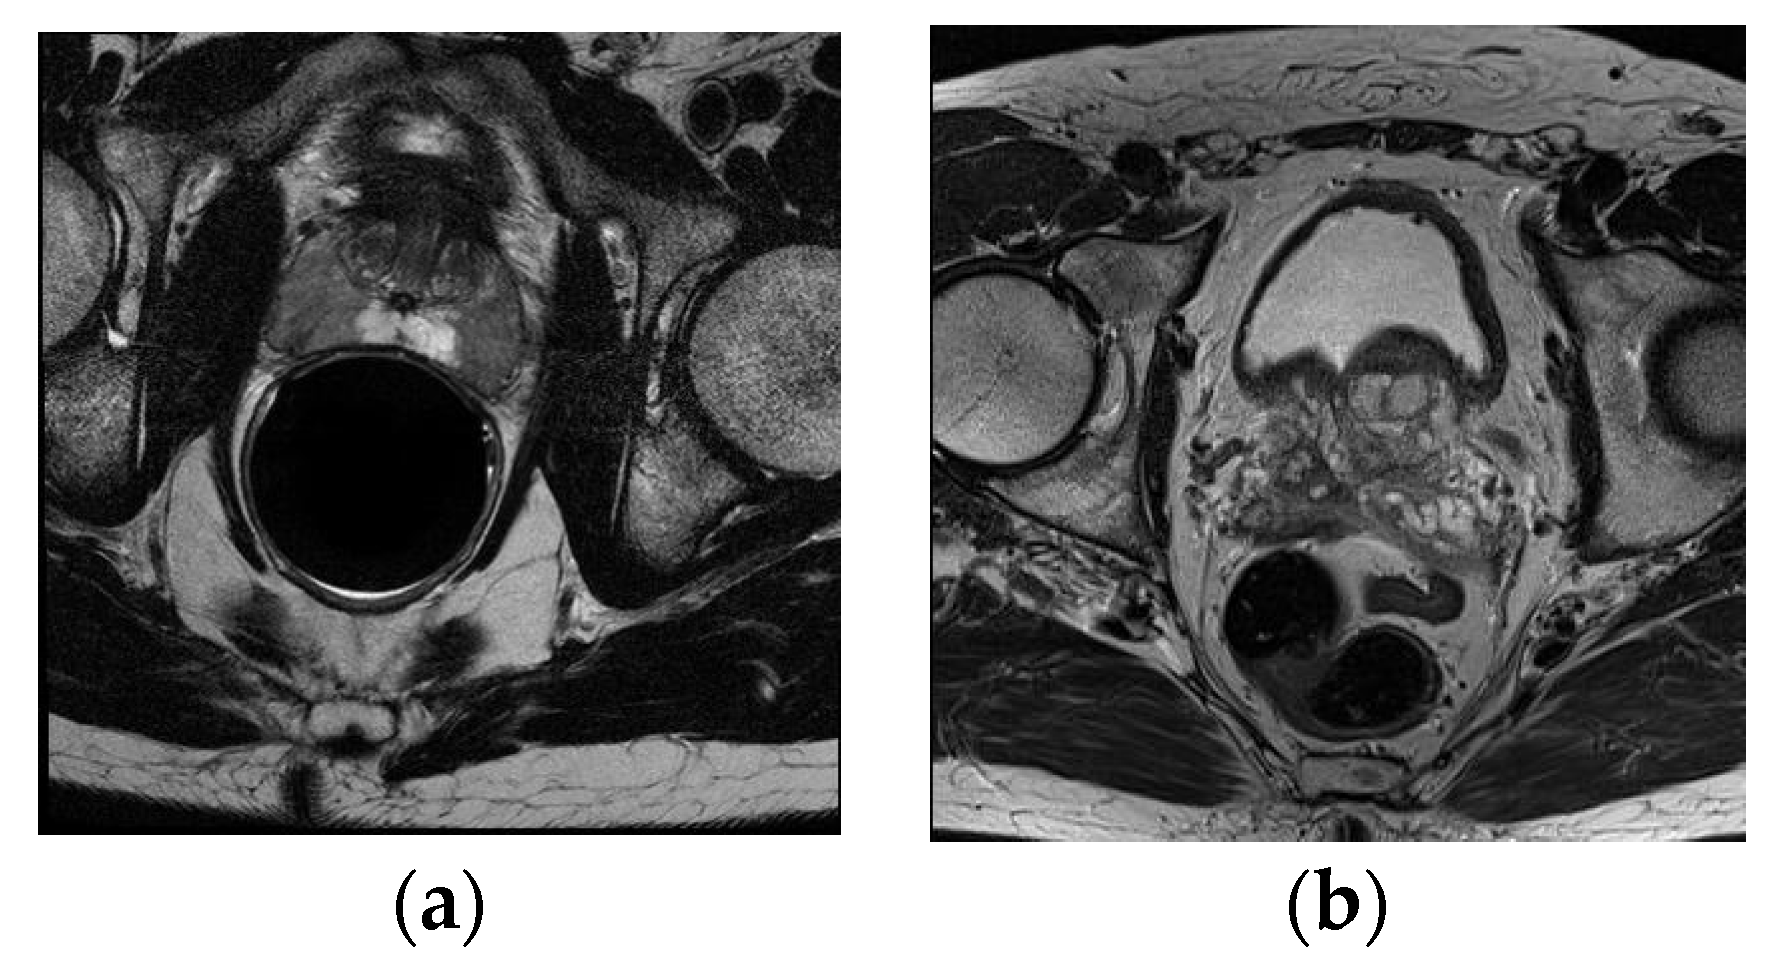

The ASPS13 dataset contains 80 T2-weighted MR images, together with the corresponding segmentation ground truth annotated by experts. All images collected in this dataset are from prostate cancer patients. Half of them were obtained at 1.5 T Philips Achieva with an ERC from Boston Medical Center (BMC), and the other half were obtained at 3 T Siemens TIM with a surface coil (SC) from Radboud University Nijmegen Medical Center (RUNMC). They were acquired as T2-weighted MR axial pulse sequences with either 4 mm thick slices at 3 T or 3 mm thick at 1.5 T. Given that this dataset has 11 overlapped subjects with PROMISE12, we removed them in the experiment and only kept the remaining 69 samples. Figure 2 shows one scan from each center.

Figure 2. Example image slices from ASPS13 dataset. (a) 1.5 T with ERC from BMC; (b) 3.0 T with SC from RUNMC.